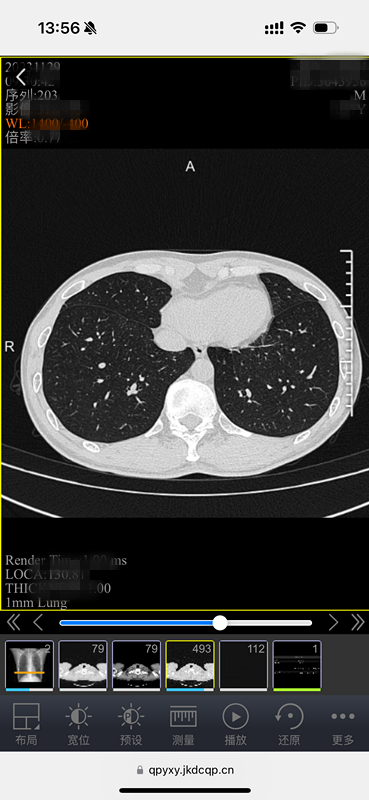

原来,这是中山医院青浦分院为方便百姓就医、优化就诊流程,推出的又一项便民措施——“电子胶片”智慧医疗服务。放射科主任武刚介绍,所谓“电子胶片”,就是患者在中山医院青浦分院做了放射DR、CT、磁共振等检查后,无需再去窗口等待打印传统胶片,用手机、ipad等移动终端扫描报告单上的二维码,检查的影像资料就可以全部在手机上显示,临床医生也可以使用电脑查看影像资料。

电子胶片,不光保存方便,携带方便,医生还能看原始数据。什么叫原始数据?简单地说就是“电子胶片”包含全部图像,支持对图像进行放大缩小、调节明暗等专业操作,能更好地看清病灶,更利于诊断。